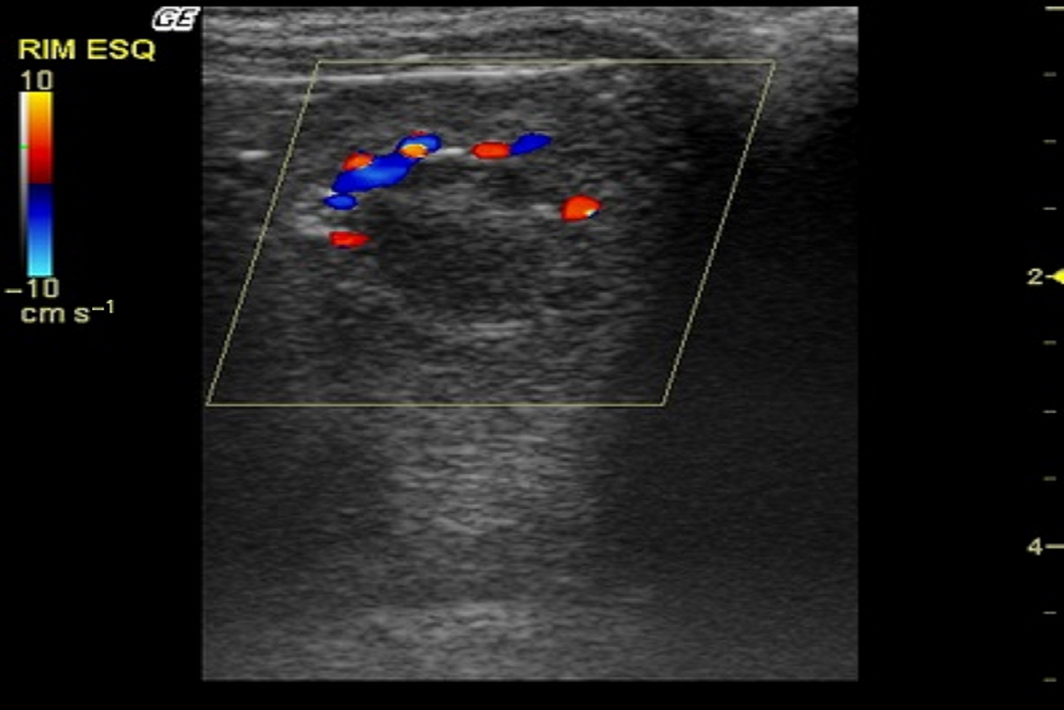

After the B-mode examination, the kidneys were assessed by colour Doppler mode. The hilar and intrarenal vasculature was visualized. At the hilum, it was possible to define the renal artery and renal vein. Cortical and medullary regions were observed presenting several vascular branches, both arterial and venous, throughout the renal parenchyma (Fig. 3). No sign of turbulence was observed. Spectral Doppler mode examination measured systolic peak velocity (Vs), end diastolic velocity (Vd) and resistive index (RI [range: 46–56, mean 53]) of the renal artery. The spectral Doppler measurements of the left renal artery are described in Table 1.

Figure 3.

Color Doppler sonogram of the left kidney in an Alouatta fusca. Cortical and medullary regions were observed demonstrating arcuate vessels at the cortico-medullary junction.